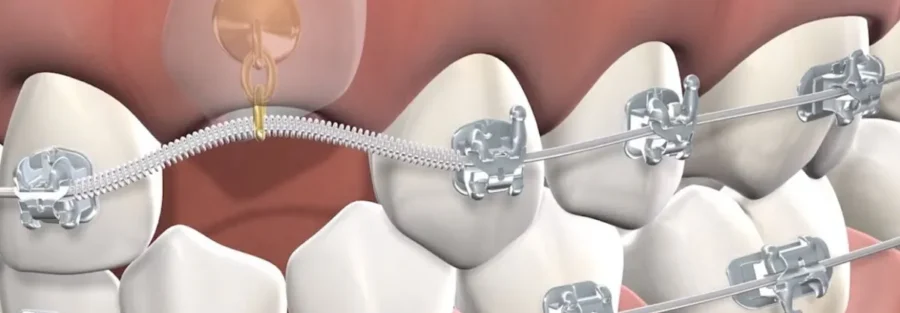

- ارتودنسی ثابت دندان: استفاده از براکتها برای هدایت دندان نهفته به جای مناسب

- استفاده از نگهدارندهها و کشهای ارتودنسی: برای کنترل و هدایت دقیق دندان

این روشها معمولاً با برنامهریزی دقیق و نظارت متخصص ارتودنسی انجام میشوند تا دندان نهفته به موقعیت صحیح خود برسد و سلامت فک و دندانهای مجاور حفظ شود.